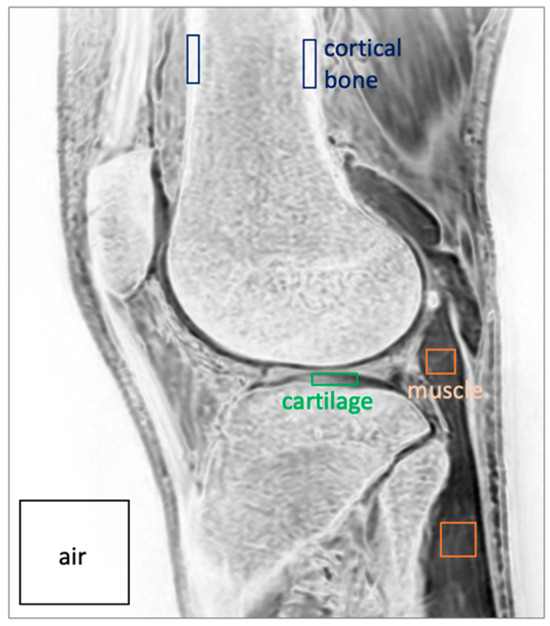

| Mean (+/−Std. Dev.) Values for Each Sequence | ANOVA | |||

|---|---|---|---|---|

| Measurement | δUTE processed | FE processed | FE HR-DLR processed | p-value |

| Bone SNR | 104 (19.3) | 304 (271) | 410 (179) | 0.086 |

| Muscle SNR | 63.1 (22.2) | 116 (70.0) | 168 (64.4) | 0.716 |

| Cartilage SNR | 69.8 (23.5) | 166 (141) | 233 (96.1) | 0.067 |

| Bone-Muscle CNR | 40.5 (8.4) | 187 (205) | 242 (139) | 0.137 |

| Bone-Cart CNR | 33.8 (6.6) | 138 (148) | 177 (103) | 0.124 |